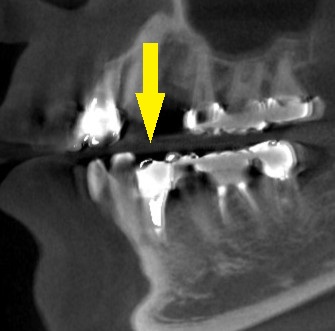

下の写真が、手術前後のCTです。